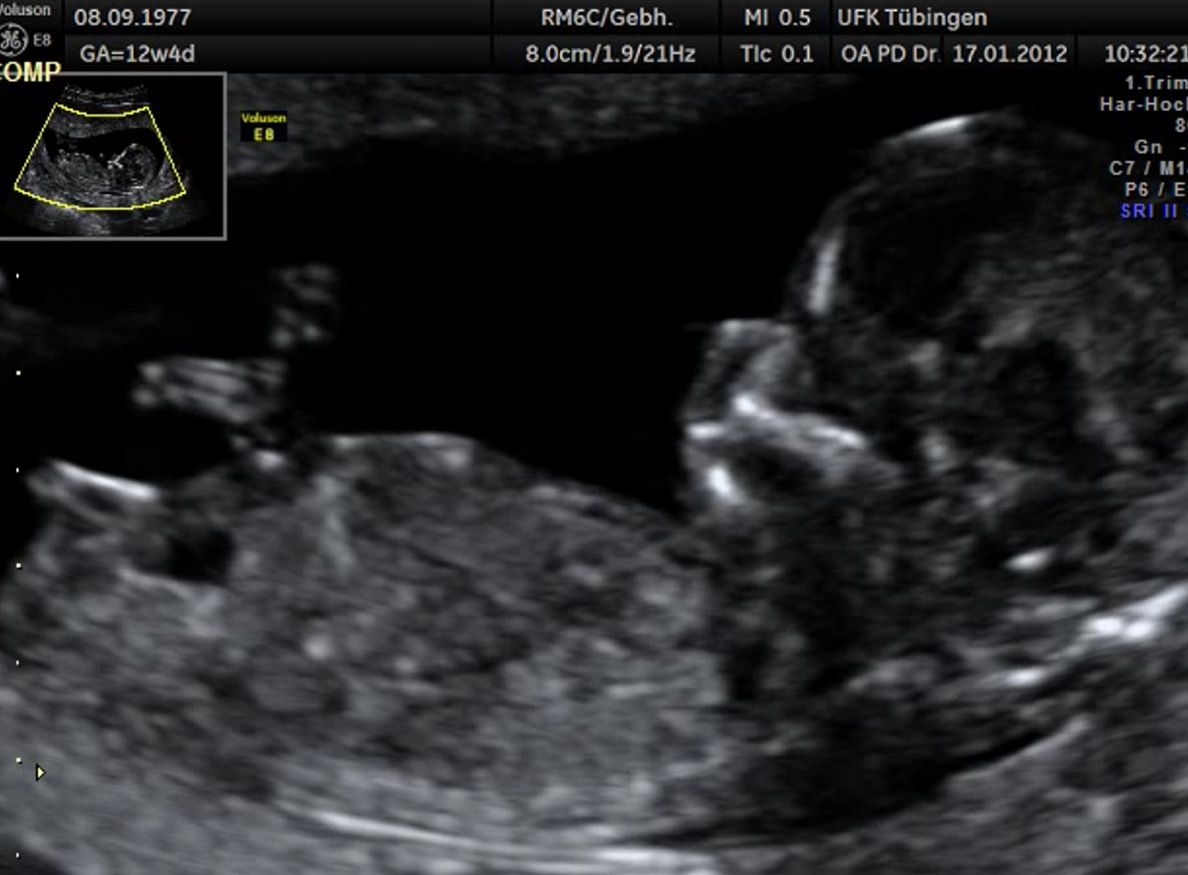

Das Ergebnis der Ultraschalluntersuchung ist wegweisend. Dabei wird der Fet vermessen, die Organe werden untersucht und die sonographischen Marker zur Risikoberechnung für Chromosomenstörungen werden beurteilt. Das sind: die Nackentransparenzdicke, Nasenbein sowie der Blutfluss in der rechten Herzhälfte und im Ductus venosus, einem Gefäß in der Leber des Feten.

Findet sich eine Fehlbildung oder ist die Nackentransparenzdicke deutlich erhöht, werden wir mit Ihnen eine Abklärung mittels Fruchtwasser- oder Mutterkuchenpunktion besprechen. Ob diese dann tatsächlich durchgeführt wird, müssen wir in einem gemeinsamen Gespräch klären.